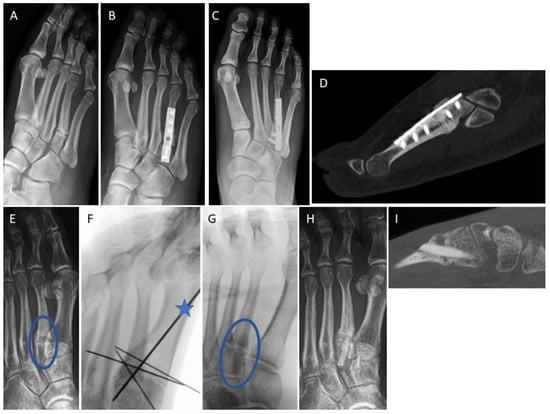

3.4. Examples for Bone Healing

3.6. Radiological Findings of Interest